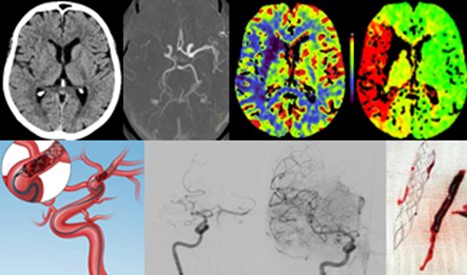

Akute Schlaganfallbehandlung

Mechanische Thrombektomie

Beim akuten ischämischen Schlaganfall – in den Industrieländern immerhin die dritthäufigste Todesursache und im Erwachsenenalter die häufigste Ursache einer bleibenden Behinderung – hat die interventionelle Therapie innerhalb der letzten Jahre einen rasanten Aufschwung erfahren. Schwer betroffene Schlaganfallpatientinnen und -patienten profitieren erheblich von der Katheterbehandlung und sind nach dieser Therapie signifikant weniger eingeschränkt bzw. im Alltag häufiger unabhängig. Ausgewählte Patientinnen und Patienten können sogar selbst im erweiterten Zeitfenster bis 24 Stunden nach Symptombeginn profitieren. Dadurch haben sich die therapeutischen Möglichkeiten für Schlaganfallpatientinnen und -patienten grundlegend geändert.

Mittlerweile belegen zahlreiche internationale Studien den besonderen Erfolg der Thrombektomie und auch in den deutschen und europäischen Leitlinien zur Schlaganfalltherapie ist diese Behandlungsform schon fest etabliert. In den größeren Schlaganfallzentren ist die mechanische Thrombektomie wichtiges Strukturmerkmal und häufig ein entscheidender Erfolgsfaktor, ob der Schlaganfall ohne Behinderung überstanden wird, so auch im Klinikum Bayreuth an der Betriebsstätte Klinik Hohe Warte.

Die Katheterbehandlung ist bei schwer betroffenen Patientinnen oder Patienten mit einem großen Gefäßverschluss die Therapie der Wahl mit oder ohne einer vorher begonnenen medikamentösen Lyse-Therapie. Neben der klinischen Untersuchung bildet die Bildgebung mit CT und CT-Angiographie die Grundlage für die Therapieentscheidung. In enger interdiziplinärer Zusammenarbeit der Klinik für Neurologie, dem Institut für Radiologie und Neuroradiologie und der Klinik für Anästhesiologie werden die Patientinnen und Patienten optimal versorgt. Rasches Handeln und optimale Abläufe sind dabei entscheidend, um die Therapie schnellstmöglich durchzuführen, denn es gilt dabei immer:

TIME IS BRAIN!